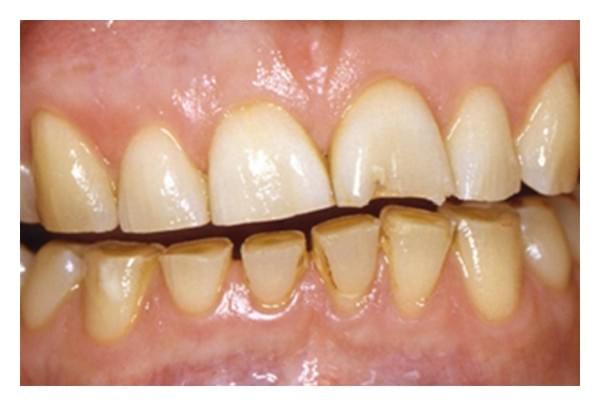

- Gum Diseases - Gum diseases can be roughly classified into 2 categories: - 1. Gingivitis - a reversible form of gum disease caused by dental plaque, usually appears as bleeding when brushing and redness of gums - 2. Periodontitis* - an irreversible, advanced form of gum disease that involves pocket formation, gum recession and bone loss, resulting in mobility and subsequent loss of teeth  - Risk factors including genetics, poor oral hygiene, smoking and poorly controlled diabetes can increase the risk of development/severity of gum diseases/treatment outcome. - *Requires ongoing reviews and further management by dental practitioners  - A periodontal chart is required to understand the extent and severity before intervention.  - Advanced gum disease with heavy calculus/tartar deposits and gum recession: gums appear red and swollen.